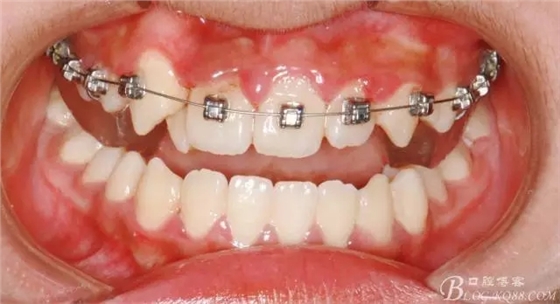

牽引側(cè)切牙時(shí)要保持中線的位置;

640.webp (7).jpg

矯正過程中對(duì)牙周進(jìn)行了手術(shù)治療;